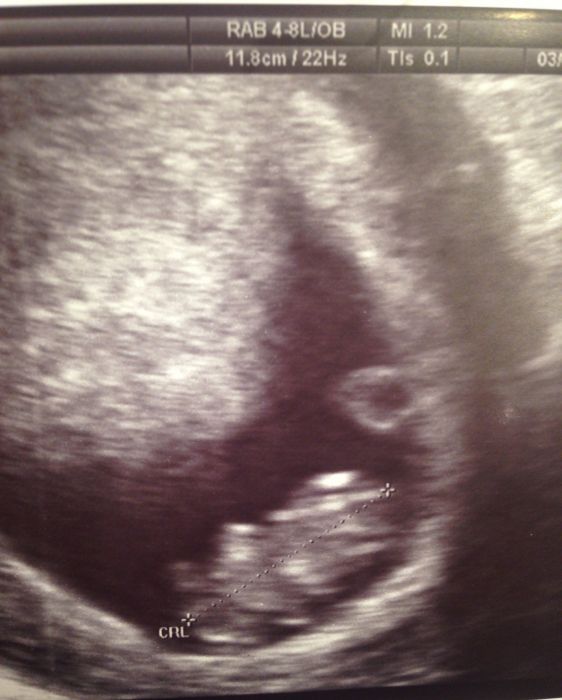

Ahoj holky, v týdnu jsem byla na kontrole, brali mi krev a dělali uz a vše je v pořádku. Posílám obrázek. Na ultrzvuku bylo vidět jak mává ručkama a kope nožičkama, řikala jsem si jestli je to vůbec možný? :) Pěkný a klidný víkend přeji :)

Erika: moc hezká fotka, taky si kolikrát říkáme, jak je možné, že tak malé miminko velké asi jako hrozen už má vše funkční a je to vlastně takový malý človíček